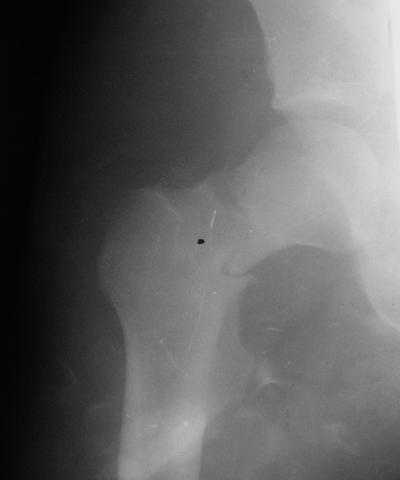

Уважаемые коллеги!молодой человек 22 лет обратился к нам с жалобами на умеренную боль в в/3 левого бедра и паху при ходьбе, укорочение левой ноги. 3 года назад получил закрытый перелом шейки левого бедра (рис 1).

Лечился в стержневом аппарате по месту жительства. АВФ демонтировали через полгода из-за воспаления в области стержней (рис 2). После демонтажа в течение месяца больной лихорадил до 38*, были боли в бедре. Эти явления исчезли после курса антибиотиков. Через год после травмы в ЦРБ ему имплантировали биполярный протез (рис 3). Рана зажила первично. Ходил с костылями, слегка приступая на ногу. На контрольных осмотрах выявлена прогрессирующая протрузия (рис 4-6).